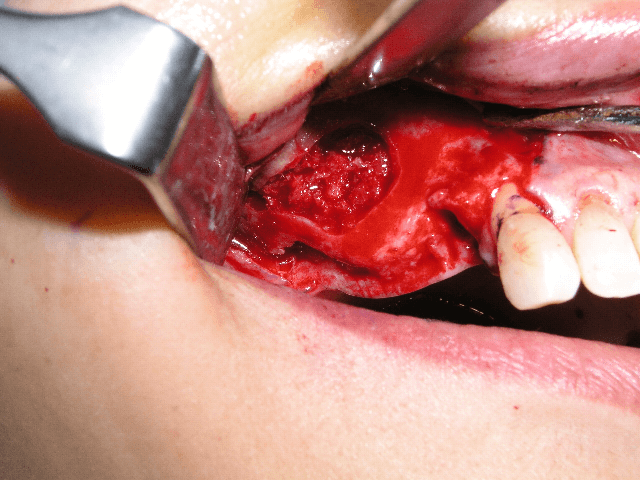

1983年に東京歯科大学が日本で最初にオッセオインテグレーテッドインプラントの概念とその治療法を紹介して以来、口腔インプラント療法は急速な進歩を遂げ、現在では、咀嚼障害や審美障害の改善手段として、長期間にわたる良好な治療成績が確認されています。千葉歯科医療センター口腔インプラント科では、近年、ますます複雑、多様化する患者様のニーズに応えるため、最新の設備や充実したスタッフを配備し、安心・快適・便利を実感できる診療科をめざしています。また、インプラント埋入手術時の鎮静法の併用、基礎疾患を持っている患者様の全身管理下での処置、骨移植、口腔内軟組織移植等の関連手術を行う設備体制を整え、大学医療機関の特色と利点を最大限に生かした治療を心がけています。

1~2本と歯の欠損が少ない場合でのインプラント治療は、従来の治療法(ブリッジや入れ歯)と比較して両隣の歯を削ったりする必要がなく、残っている歯に負担をかけないですみます。また、前歯の治療においては隣在歯と調和のとれた高い審美回復が必要とされることから、骨と粘膜の高度なマネージメントが必要とされます。口腔インプラント科では、高いレベルの審美修復治療の結果を達成するよう専門スタッフが対応しています。

部分入れ歯や総入れ歯などを使う必要がある歯の欠損に対するインプラント治療では、入れ歯と比較して違和感が少なく、咀嚼や発音などの機能回復が期待できます。また、欠如部以外の残存歯の治療が必要になる場合も、初診時からメンテナンスに至るまで一貫した包括的治療を行っています。また、インプラント埋入部位の骨が不足していたり、その他の要因でインプラント療法を断念されていた患者様に対しても、各分野の専門スタッフが高度な診断技術により対応をしています。